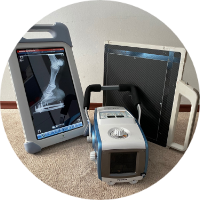

Radiología Digital Directa

Radiología Digital Directa

Posteriormente la radiología computarizada evolucionó a la radiología digital directa en donde podíamos hacer placas radiográficas y ver las imágenes en aproximadamente 18-20 segundos después de tomar la radiografía, y esto fue un gran avance para la comunidad de médicos, veterinarios, antropólogos, restauradores, paleontólogos, investigadores, y gente que requería radiografías y que por la logística que se requería y lo que implicaba no utilizaba esta herramienta de diagnóstico. En la actualidad, en la era de la inmediateidad podemos tomar placas radiográficas de alta definición en 2-3 segundos, en lugares remotos, sin necesidad de energia electrica ya que los generadores de rayos X funcionan con baterías, así como los equipos de radiología digital directa, esto ha permitido que el servicio de radiología se pueda proporcionar en cualquier lugar donde se requiera, pudiendo llevarse a donde están los pacientes u objetos a radiografiar, con las ventajas que esto implica. Los equipos actuales son ligeros, portátiles, de alta frecuencia, de alta definición, se ha optimizado la radiación que generan, lo que permite obtener imágenes radiográficas de muy buena calidad, con técnicas radiográficas inferiores a lo que se requería con radiología análoga. Hoy en día manejamos radiología digital directa de alta resolución.

Somos una empresa con más de 10 años de experiencia en radiología digital directa, dedicada a apoyar a médicos humanos, médicos veterinarios, antropólogos, biólogos, geólogos, paleontólogos, restauradores, anticuarios, peritos en obras de arte, que requieran realizar placas radiográficas digitales directas, in situ para analizar y en su caso, confirmar el diagnóstico o como ayuda complementaria en la evaluación de sus pacientes, obras de arte, esculturas, retablos, relicarios, cristos de caña, etc.

Dada la portabilidad de los equipos podemos proveer el servicio en cualquier lugar donde se requiera, nuestros equipos son portátiles y podemos tomar radiografías, desde un animal exótico hasta retablos en andamios a la altura que se requiera, nuestros equipos pueden funcionar en lugares con energia eléctrica o incluso sin energía eléctrica, facilitando el trabajo ambulatorio o el el trabajo de campo.

Radiografiamos todo lo que se pueda radiografiar. Para ver lo que no se ve.